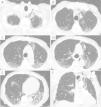

A 88-year-old male, non-smoker, without any underlying lung disease, was hospitalized due to COVID-19 pneumonia, with persistent fever and progressive fatigue. He started treatment with hydroxychloroquine, lopinavir/ritonavir, azithromycin and ceftriaxone, assuming bacterial co-infection. However, there was a radiological and analytical worsening. We switched antibiotherapy to ceftazidime and started corticosteroids, with further analytical and imaging improvement, but maintenance of hypoxemia. A chest CT angiography (Fig. 1) was performed, revealing a pneumomediastinum. After three days of rest and oxygen therapy, patient's hypoxemia improved, with overall good clinical and imaging outcome, showing spontaneous resolution. Because no precipitating factors were identified, as severe cough, signs of respiratory distress, high flow oxygen therapy or ventilatory support, we assumed a pneumomediastinum as a complication of COVID-19 pneumonia. This can be related to an alveolar membrane damage and rupture caused by the disease, followed by air dissection through the bronchovascular sheath into the mediastinum.1,2

Although a pneumomediastinum is a benign disease which only requires conservative treatment,1 it is important to monitor it closely when associated to COVID-19, due to the possibility of disease worsening.1,2